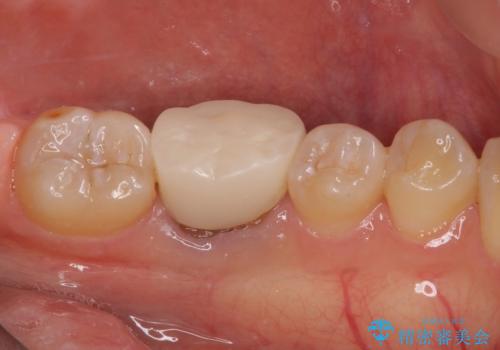

仮歯に置き換えた時点で希望に近い形態とできたので、その形を踏襲してオールセラミッククラウンを製作してもらいました。

気になっていた形が改善され、色調も自然なものとなったので、患者様には大変満足していただきました。